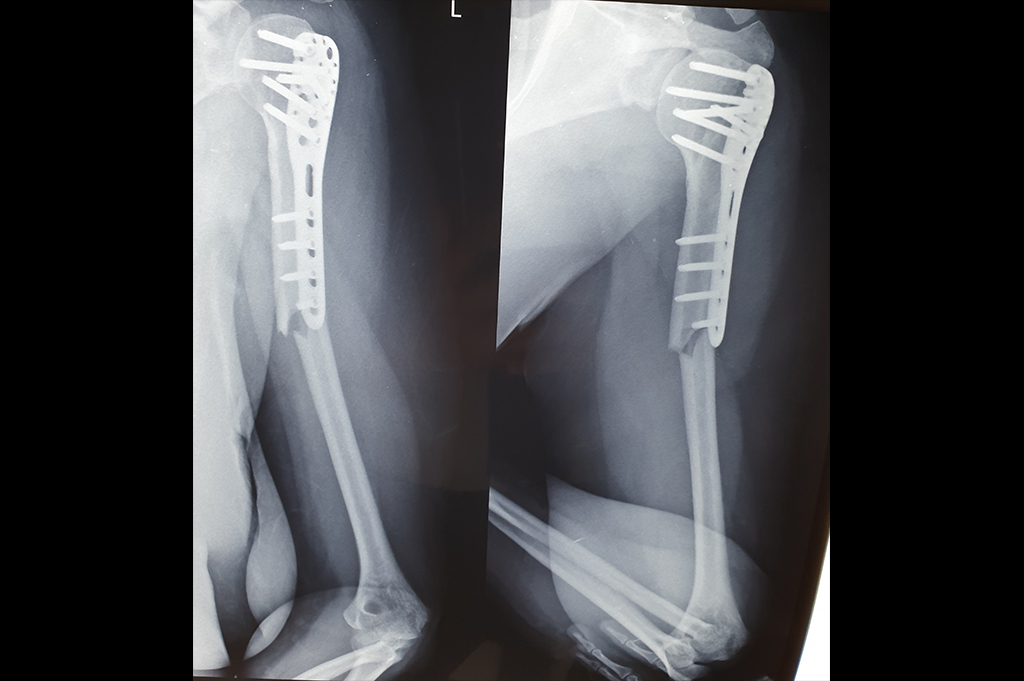

Clavicle